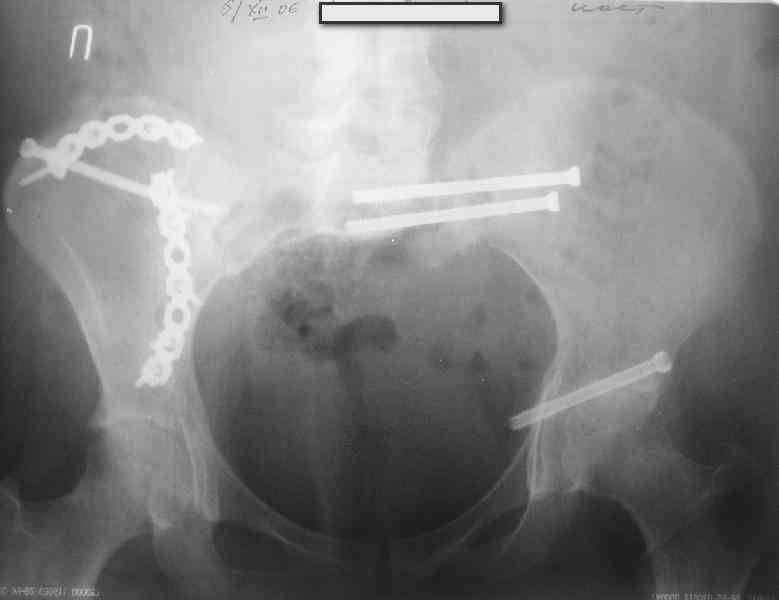

Молодая девушка 19 лет, травма 1 год назад, тогда же прооперирована.

В настоящее время имеются ноющие боли в области крестца слева, нарушение походки, ощущение неуверенности, слабости в левой нижней конечности, неврологически -непостоянные парестезии в левой нижней конечности. Ходит с дополнительной опорой, страдает от ожирения.

Какова по вашему будет оптимальная тактика в отношении несращения крестца? Замена винтов на более длинные с коррекцией их положения+ туннелизация зоны нестращения, открытое вмешательство с костной аутопластикой или еще какие варианты?

В приложении снимки при поступлении и послеоперационные год назад.

Могу сказать одно: миграция винтов и нестабильность синтеза левого подвздошно-крестцовогоо сочленения очевидна.